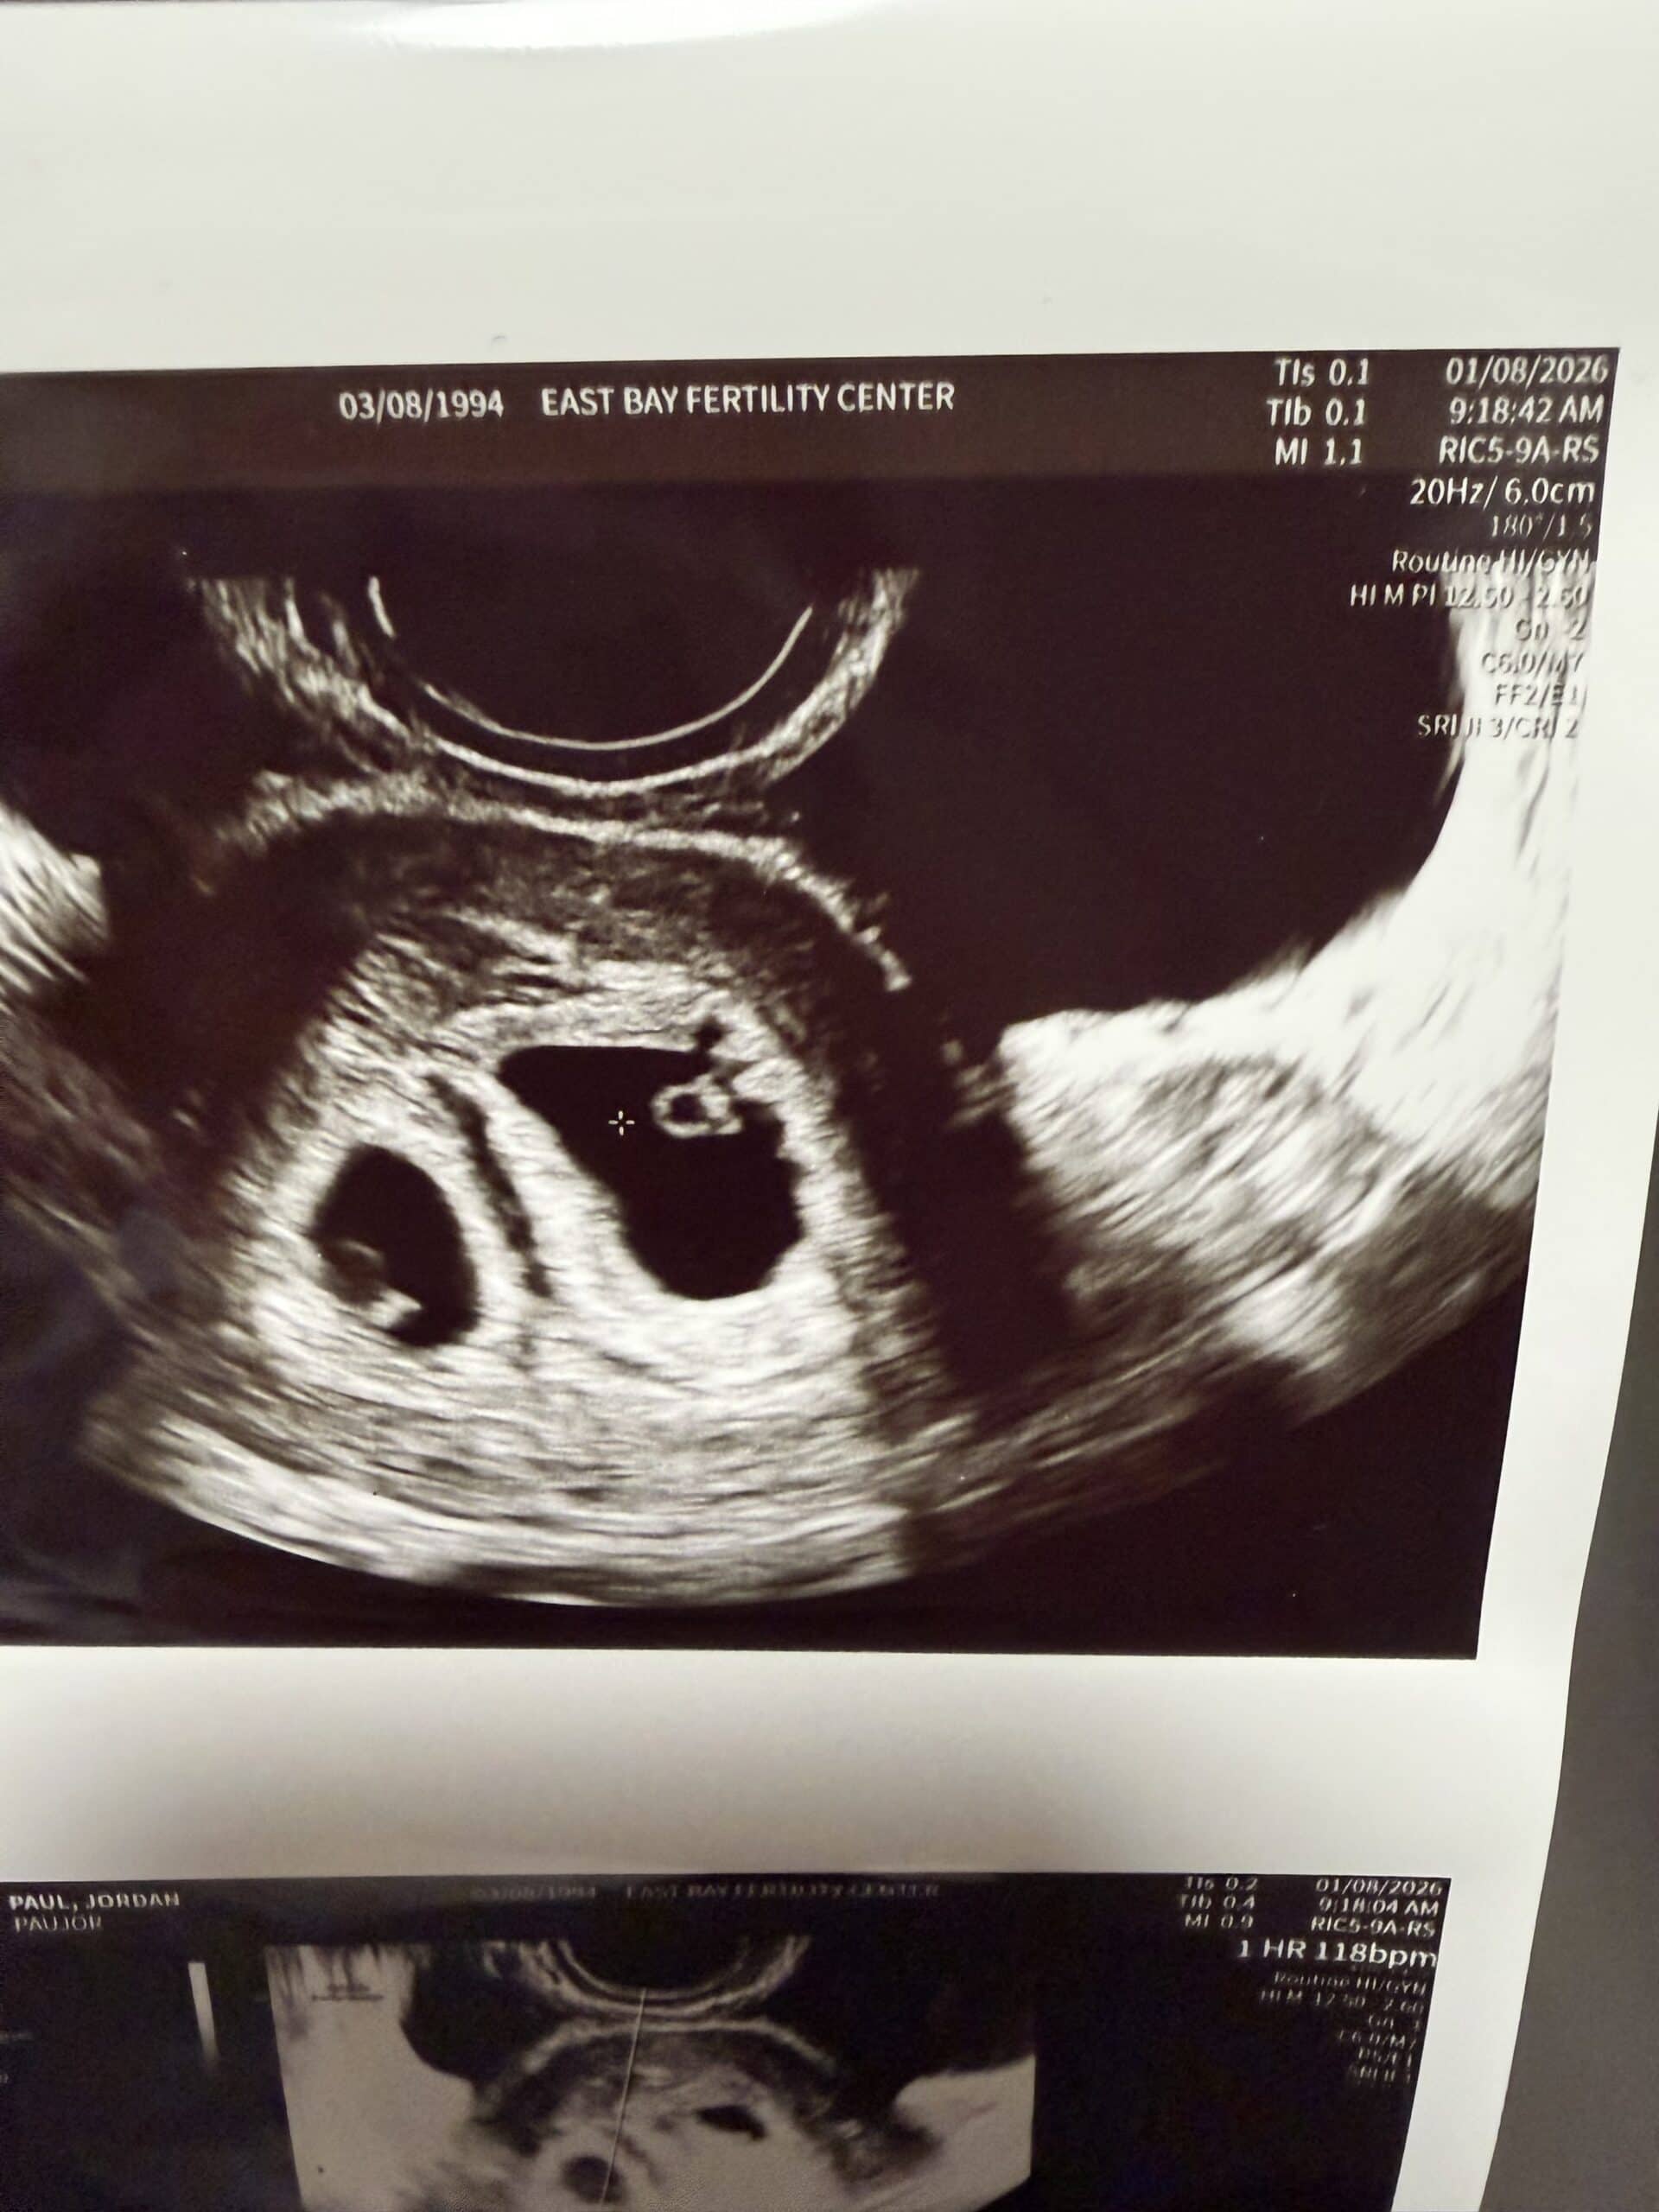

Jordan has TWO babies in the oven cooking away. LIFE in double portion. YAY God! Thank YOU, LORD!

It’s so awesome.